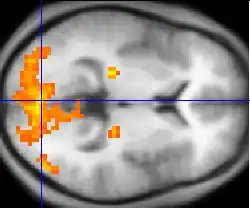

Although aphasiology is the historical core of neurolinguistics, in recent years the field has broadened considerably, thanks in part to the emergence of new brain imaging technologies (such as PET and fMRI) and time-sensitive electrophysiological techniques (EEG and MEG), which can highlight patterns of brain activation as people engage in various language tasks.[2][10][11] Electrophysiological techniques, in particular, emerged as a viable method for the study of language in 1980 with the discovery of the N400, a brain response shown to be sensitive to semantic issues in language comprehension.[12][13] The N400 was the first language-relevant event-related potential to be identified, and since its discovery EEG and MEG have become increasingly widely used for conducting language research.[14]

Hemodynamic

Hemodynamic techniques take advantage of the fact that when an area of the brain works at a task, blood is sent to supply that area with oxygen (in what is known as the Blood Oxygen Level-Dependent, or BOLD, response).[30] Such techniques include PET and fMRI. These techniques provide high spatial resolution, allowing researchers to pinpoint the location of activity within the brain;[2] temporal resolution (or information about the timing of brain activity), on the other hand, is poor, since the BOLD response happens much more slowly than language processing.[11][31] In addition to demonstrating which parts of the brain may subserve specific language tasks or computations,[20][25] hemodynamic methods have also been used to demonstrate how the structure of the brain's language architecture and the distribution of language-related activation may change over time, as a function of linguistic exposure.[22][28]

In addition to PET and fMRI, which show which areas of the brain are activated by certain tasks, researchers also use diffusion tensor imaging (DTI), which shows the neural pathways that connect different brain areas,[32] thus providing insight into how different areas interact. Functional near-infrared spectroscopy (fNIRS) is another hemodynamic method used in language tasks.[33]